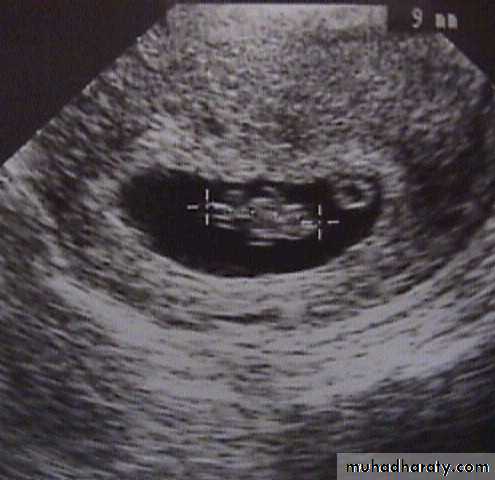

Missed abortion:

fetus dies in uterus and is retained inside uterus.

examination:uterus is smaller than expected.

Cervix is closed.

Signs:1.Uterus is smaller than period of amenorrhea (small for date uterus).

2.Cervix is closed.

Investigations:

hCG drops in 7-10 days. Positive test dose not exclude missed although negative test support diagnosis of dead fetus.

Ultrasound showed: no fetal heart and gestational sac may collapse.If there is any doubt about diagnosis, it is wise to wait for a few days and repeat scan to see if sac is growing.